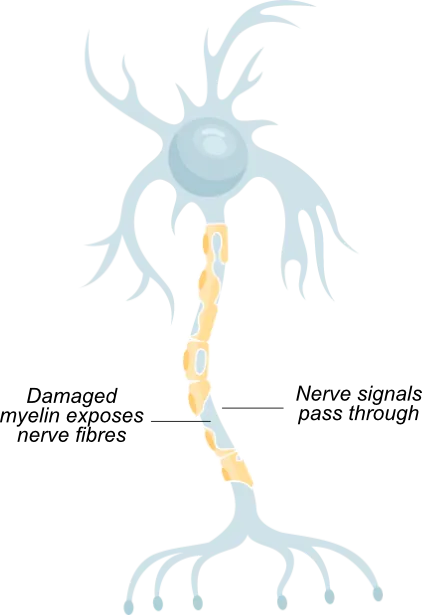

MS is an autoimmune disease that damages the myelin coating around nerve fibres, causing disruption of nerve signals

This disruption can cause problems with vision, movement, strength, coordination and thinking

Patients with MS exhibit damaged myelin and nerve fibres (demyelination)